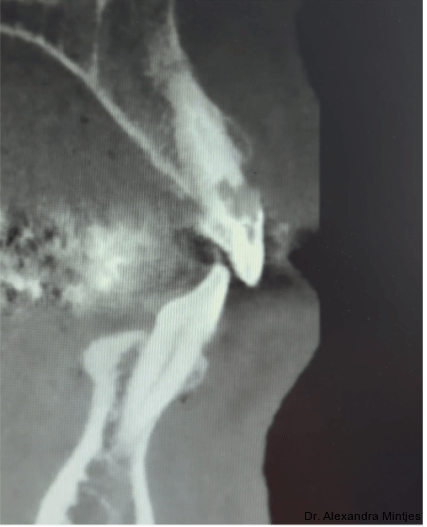

Bei der Erstvorstellung zeigte die vorhandene Füllung einen deutlichen Randspalt, war verfärbt und nach apikal hin insuffizient. Klinisch präsentierte sich ein dicker gingivaler Phänotyp mit ­harmonischer Weichgewebsbalance, jedoch bestand distal eine lokalisierte, entzündliche Zahnfleischtasche (Abb. 1). Es war zu vermuten, dass das nekrotische bzw. resorptive Hartgewebe nicht vollständig entfernt worden war. Auf dem DVT wurde das Ausmaß des Defekts deutlich. Zu­dem ließ sich eine deutliche apikale Aufhel­lung nachweisen, die Patientin war jedoch beschwerdefrei (Abb. 2).

Die Diagnose lautete eine invasive zervikale Resorption Klasse 3 nach Heithersay. Dieses Sta­-dium beschreibt eine tiefe Resorption mit Ausdehnung in das koronale Dentin und das zervikale Drittel der Wurzel, ohne dass die Pulpa vollstän­dig involviert ist. Solche Läsionen gelten als prognostisch kritisch und führen in der Regel zu einer extraktiven Therapie.